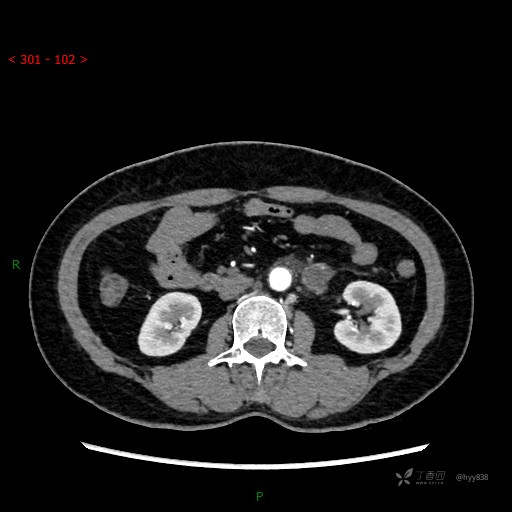

增强动脉期

CT平扫是外院的,因图像质量原因,不方便上传!